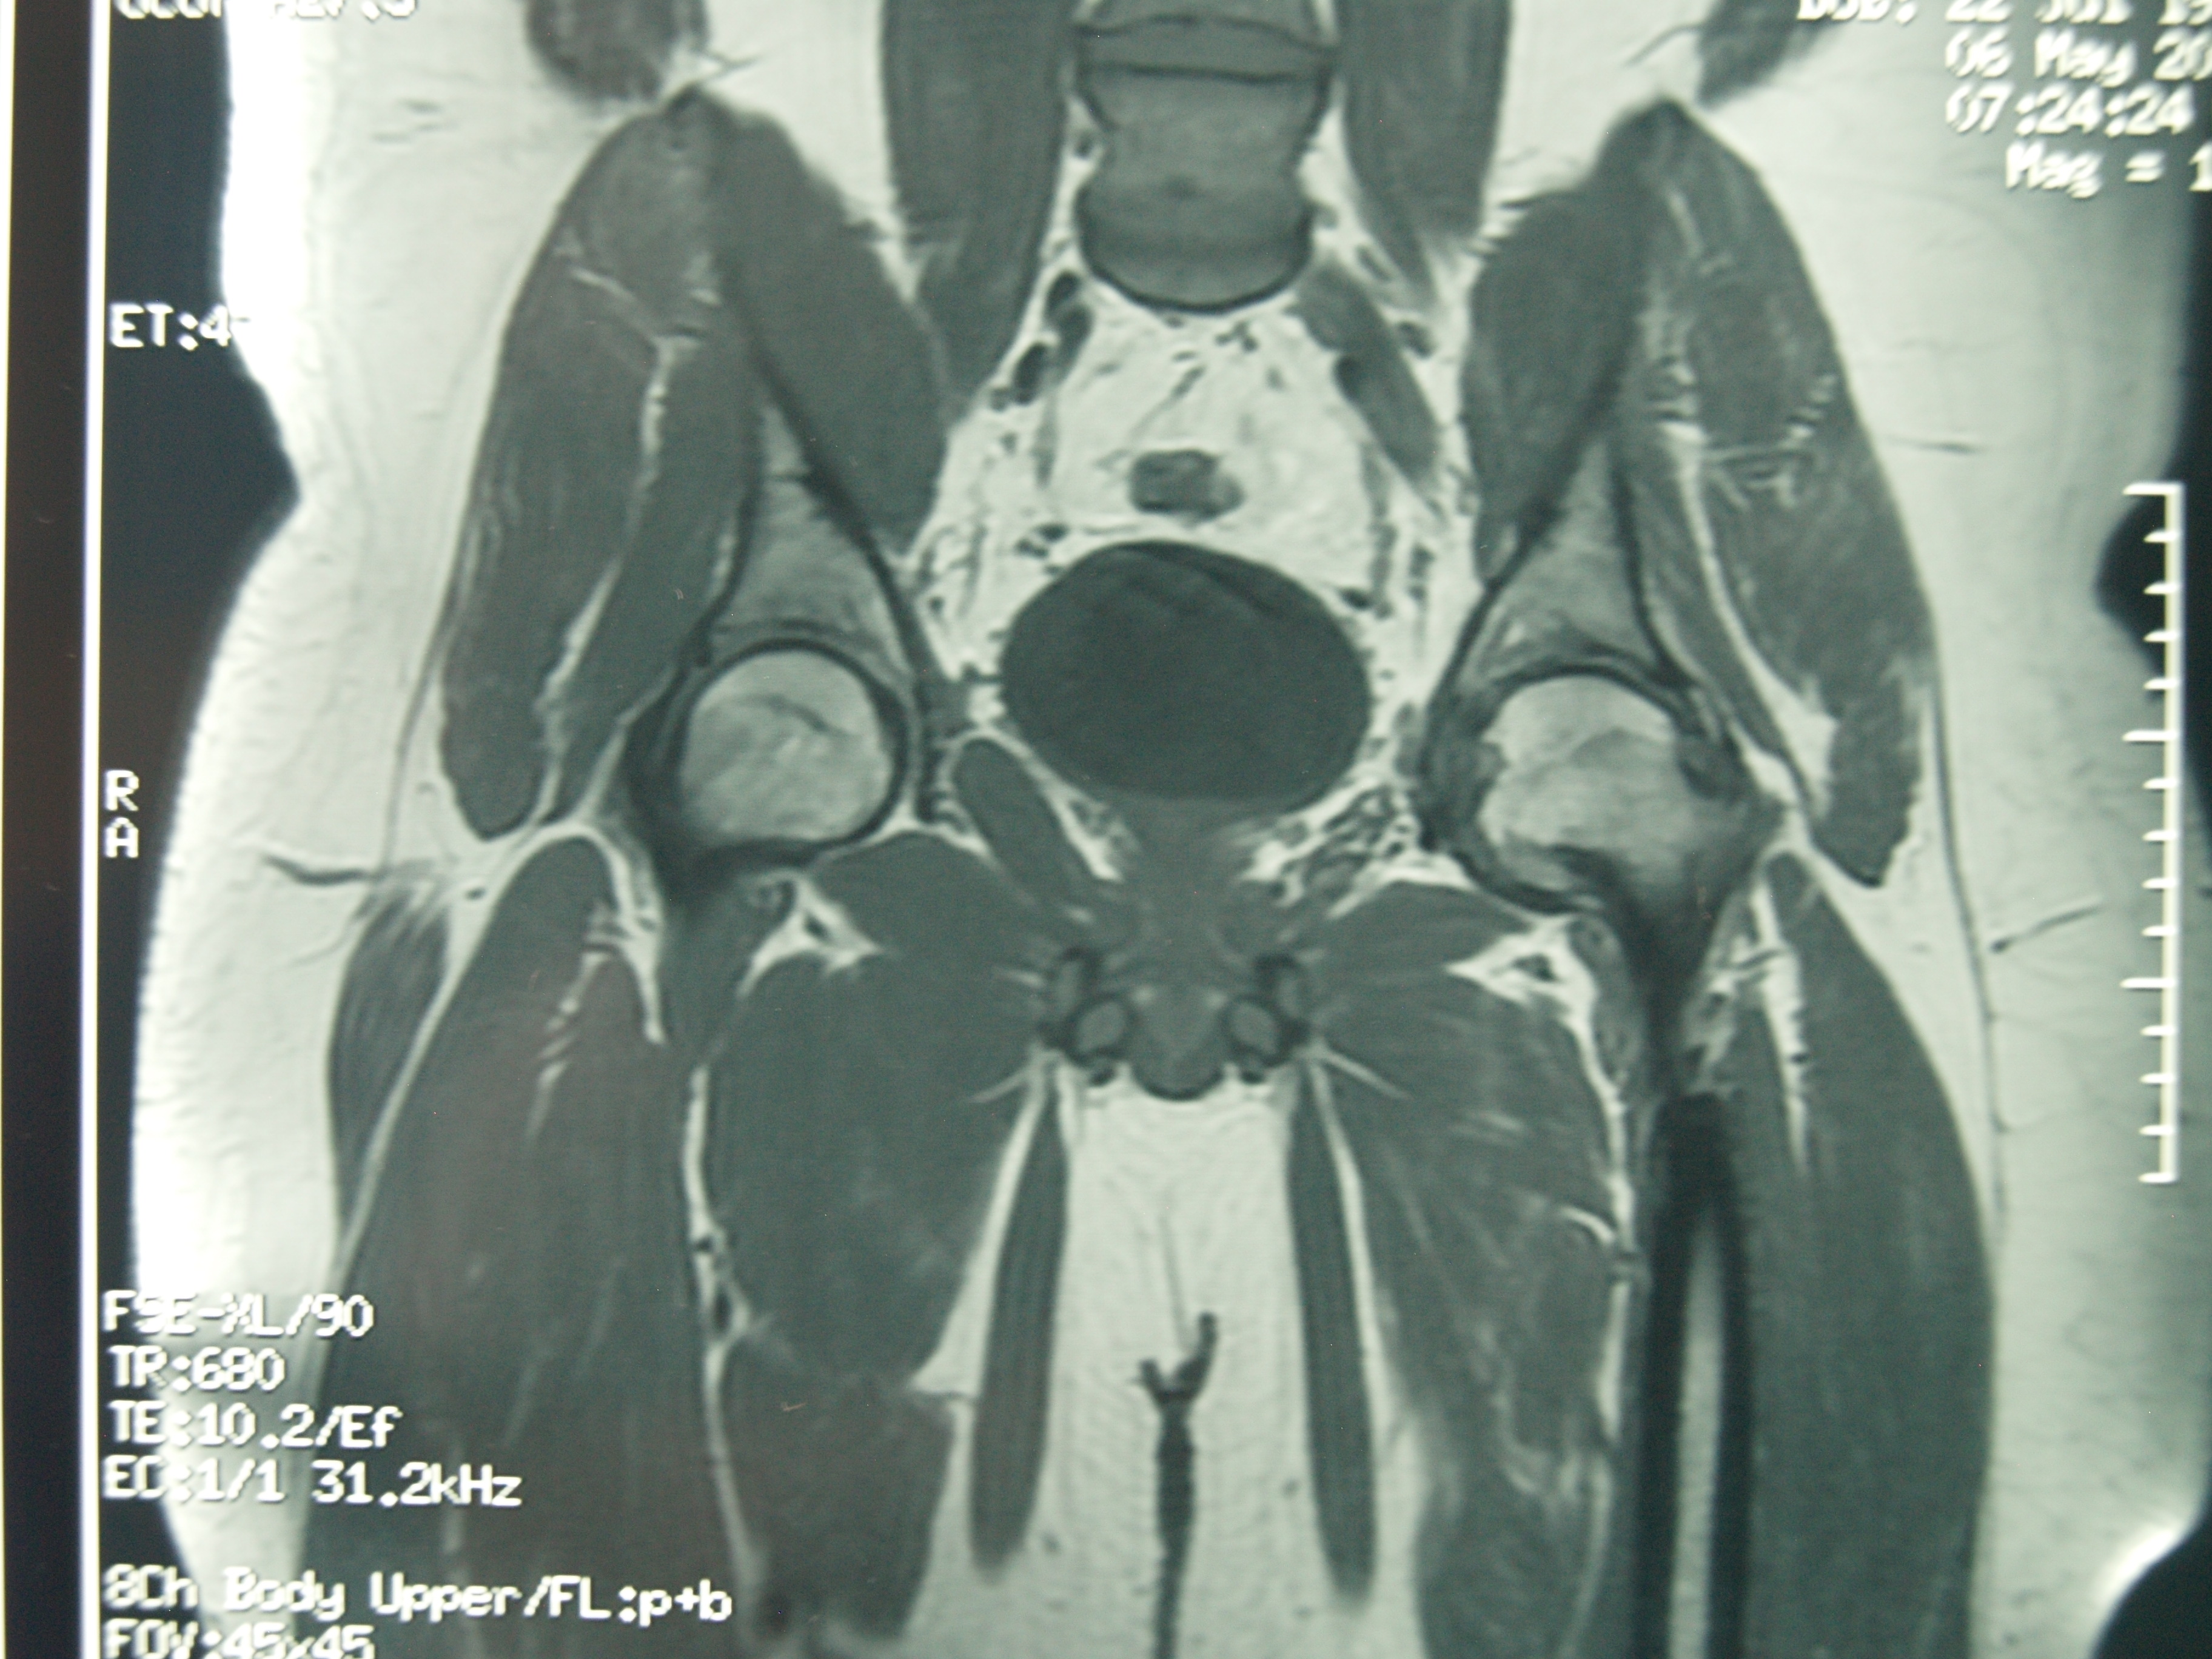

La condrolisis idiopática de cadera es una rara condición que se presenta durante la adolescencia. Se caracteriza por dolor y cojera producidos por una pérdida acelerada del cartílago articular con una disminución del grado de movilidad llegando a rigidez. La historia va desde la resolución espontánea completa a la anquilosis. El tratamiento recomendado actualmente es el conservador. Se presenta el caso clínico de un paciente de 11 años de edad con un cuadro clínico de 2 años de evolución tórpida de dolor inguinal izquierdo acompañado de cojera y rigidez. Se instauró reposo, descarga, analgésicos y rehabilitación sin mejoría inicial. Posteriormente recibió tratamiento conservador con AINE, periodos de descarga de la extremidad, tracción blanda hospitalaria, tracción ambulatoria nocturna y rehabilitación, recuperando la movilidad y marcha normal 6 años después del inicio de los síntomas. Catorce años más tarde el paciente hace una vida normal, asintomático y con movilidad simétrica de ambas caderas.